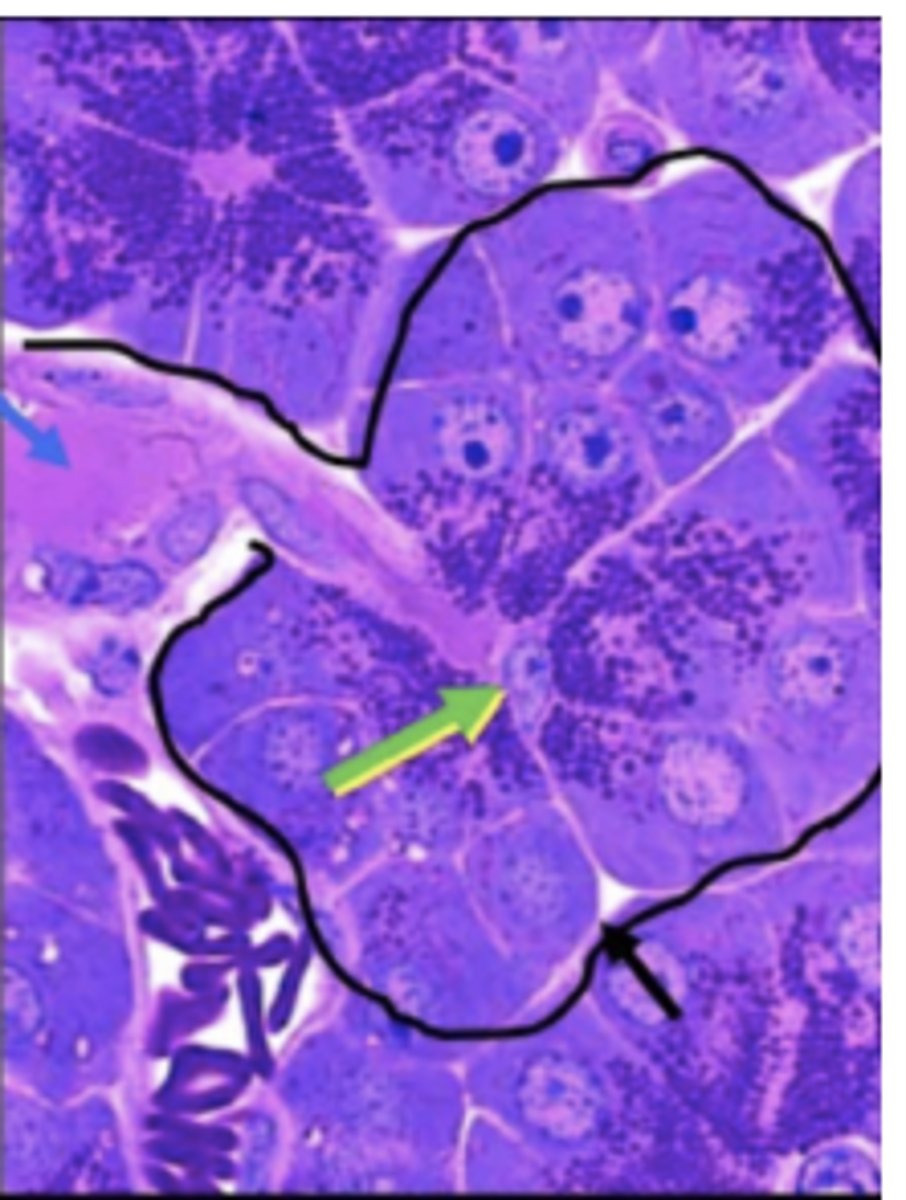

Pancreas

Centroacinar cells exclusively from which of the following organs?

green arrow = centroacinar cell